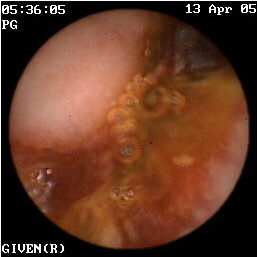

Mε βάση τις παραπάνω διεθνείς μελέτες7-13 αλλά και την εμπειρία της κλινικής μας σε 54 συνολικά ασθενείς με νόσο του Crohn, τα ευρήματα που παρατηρούνται στην εντεροσκόπηση με κάψουλα και συνηγορούν στη διάγνωση της νόσου είναι: α) οίδημα και ερυθρότητα του βλεννογόνου, β) οζώδης διαμόρφωση (εικόνες 3,4), γ) βλεννογονικές σχάσεις ή διαβρώσεις (εικόνα 5), δ) αφθώδη έλκη (ερυθηματώδης βλεννογόνος με μια λευκή κεντρική περιοχή) (εικόνες 6 -13), ε) γραμμοειδή, κυκλικά, ή ακανόνιστα έλκη (εικόνες 14-32) και στ) στενώσεις (εικόνες 33-35). Τα περισσότερα από τα παραπάνω ευρήματα παρατηρούνται στον ειλεό και ειδικά στο τελικό τμήμα του.

5  γαστρεντερολογος θεσσαλονικη

Εικόνα 5. Σχάσεις του βλεννογόνου της νήστιδας          Εικόνα 6. Αφθώδη έλκη νήστιδας